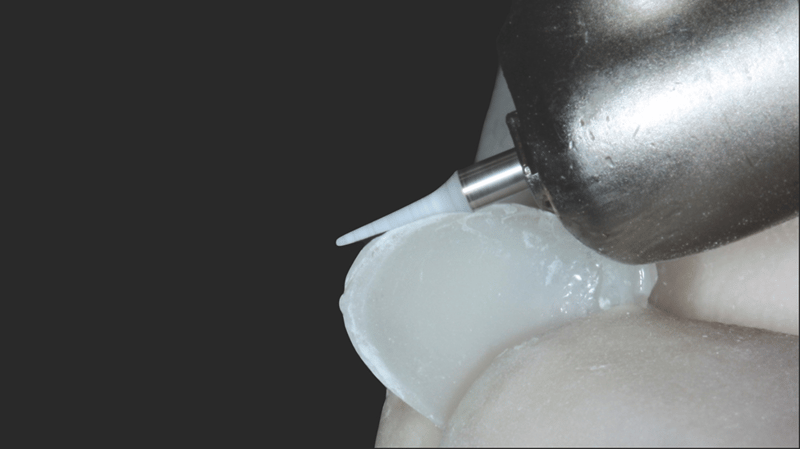

- Komposit-Applikation: Applikation von Transcend Komposit (Farbe B1D ), beginnend mit einem 2/3 Abstand von der Inzisalkante. Allmähliche Ausdünnung in Richtung Gingiva. Applikation der Farbe „Universal Body“ (UB) nahe des gingivalen Drittels. Auftragen der finalen Schichten mit Enamel White (EW) und einer kleinen Menge UB am gingivalen Rand, um einen natürlichen Farbverlauf zu erzielen.

- Präparation der Innenfläche: Behandlung der Veneer-Innenfläche mit einem Pulverstrahlgerät. Alternativ kann für diesen Schritt Ultra-Etch™ Ätzgel mit 35% Phosphorsäure verwendet werden.

- Adhäsiv-Applikation: Benetzung der Innenfläche mit Peak™ Universal Bond Adhäsiv.

- Ausdünnung und Lichthärtung des Adhäsivs: Verblasen des Adhäsivs mit einem Luftstrahl zu einer dünnen Schicht. Anschließende Lichthärtung mit der VALO™ X LED-Polymerisationsleuchte (3 Sekunden im Xtra Power Modus).